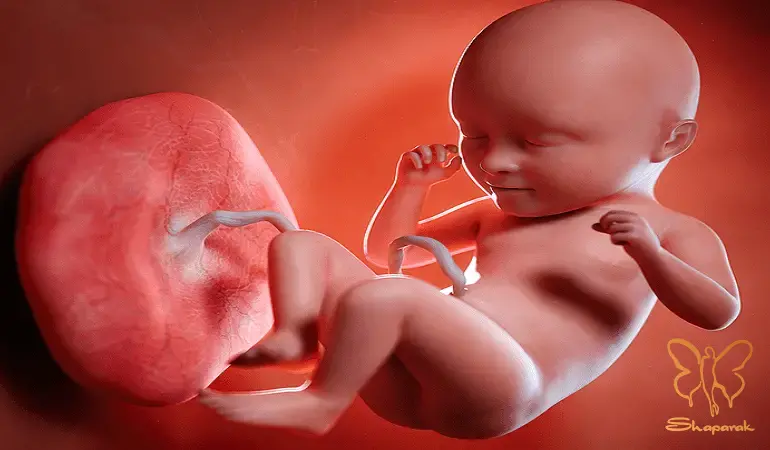

بارداری فرآیندی پیچیده و دقیق است که با لقاح آغاز می شود. در هفته های اول، این سلول به سرعت تقسیم شده و توده ای سلولی را تشکیل می دهد که در دیواره رحم لانه گزینی می کند. در کلینیک تخصصی لیزر موهای زائد شاپرک طلایی مشهد، ما معتقدیم درک این فرآیند ظریف به مادران کمک می کند تا دلیل احتیاط های پزشکی ما را بهتر درک کنند. هر گونه تداخل خارجی، استرس یا ورود مواد شیمیایی ناشناخته در این مراحل اولیه (به ویژه سه ماهه اول که اندام های حیاتی در حال شکل گیری هستند) می تواند ریسک های جبران ناپذیری ایجاد کند. برای درک اینکه چرا خدمات زیبایی مانند: تزریق ژل، بوتاکس یا مواد مزوتراپی و... در دوران بارداری ممنوع است، باید بدانیم جنین چگونه تغذیه می کند. جفت (Placenta) عضوی شگفت انگیز است که رابط بین خون مادر و خون جنین است. اکسیژن و مواد مغذی از طریق بند ناف به جنین می رسد و مواد زائد دفع می شود. اگرچه جفت مانند: یک فیلتر عمل می کند، اما سدی نفوذناپذیر نیست. بسیاری از داروها، مواد شیمیایی ریزمولکول و حتی هورمون های استرس می توانند از سد جفت عبور کرده و وارد جریان خون جنین شوند.